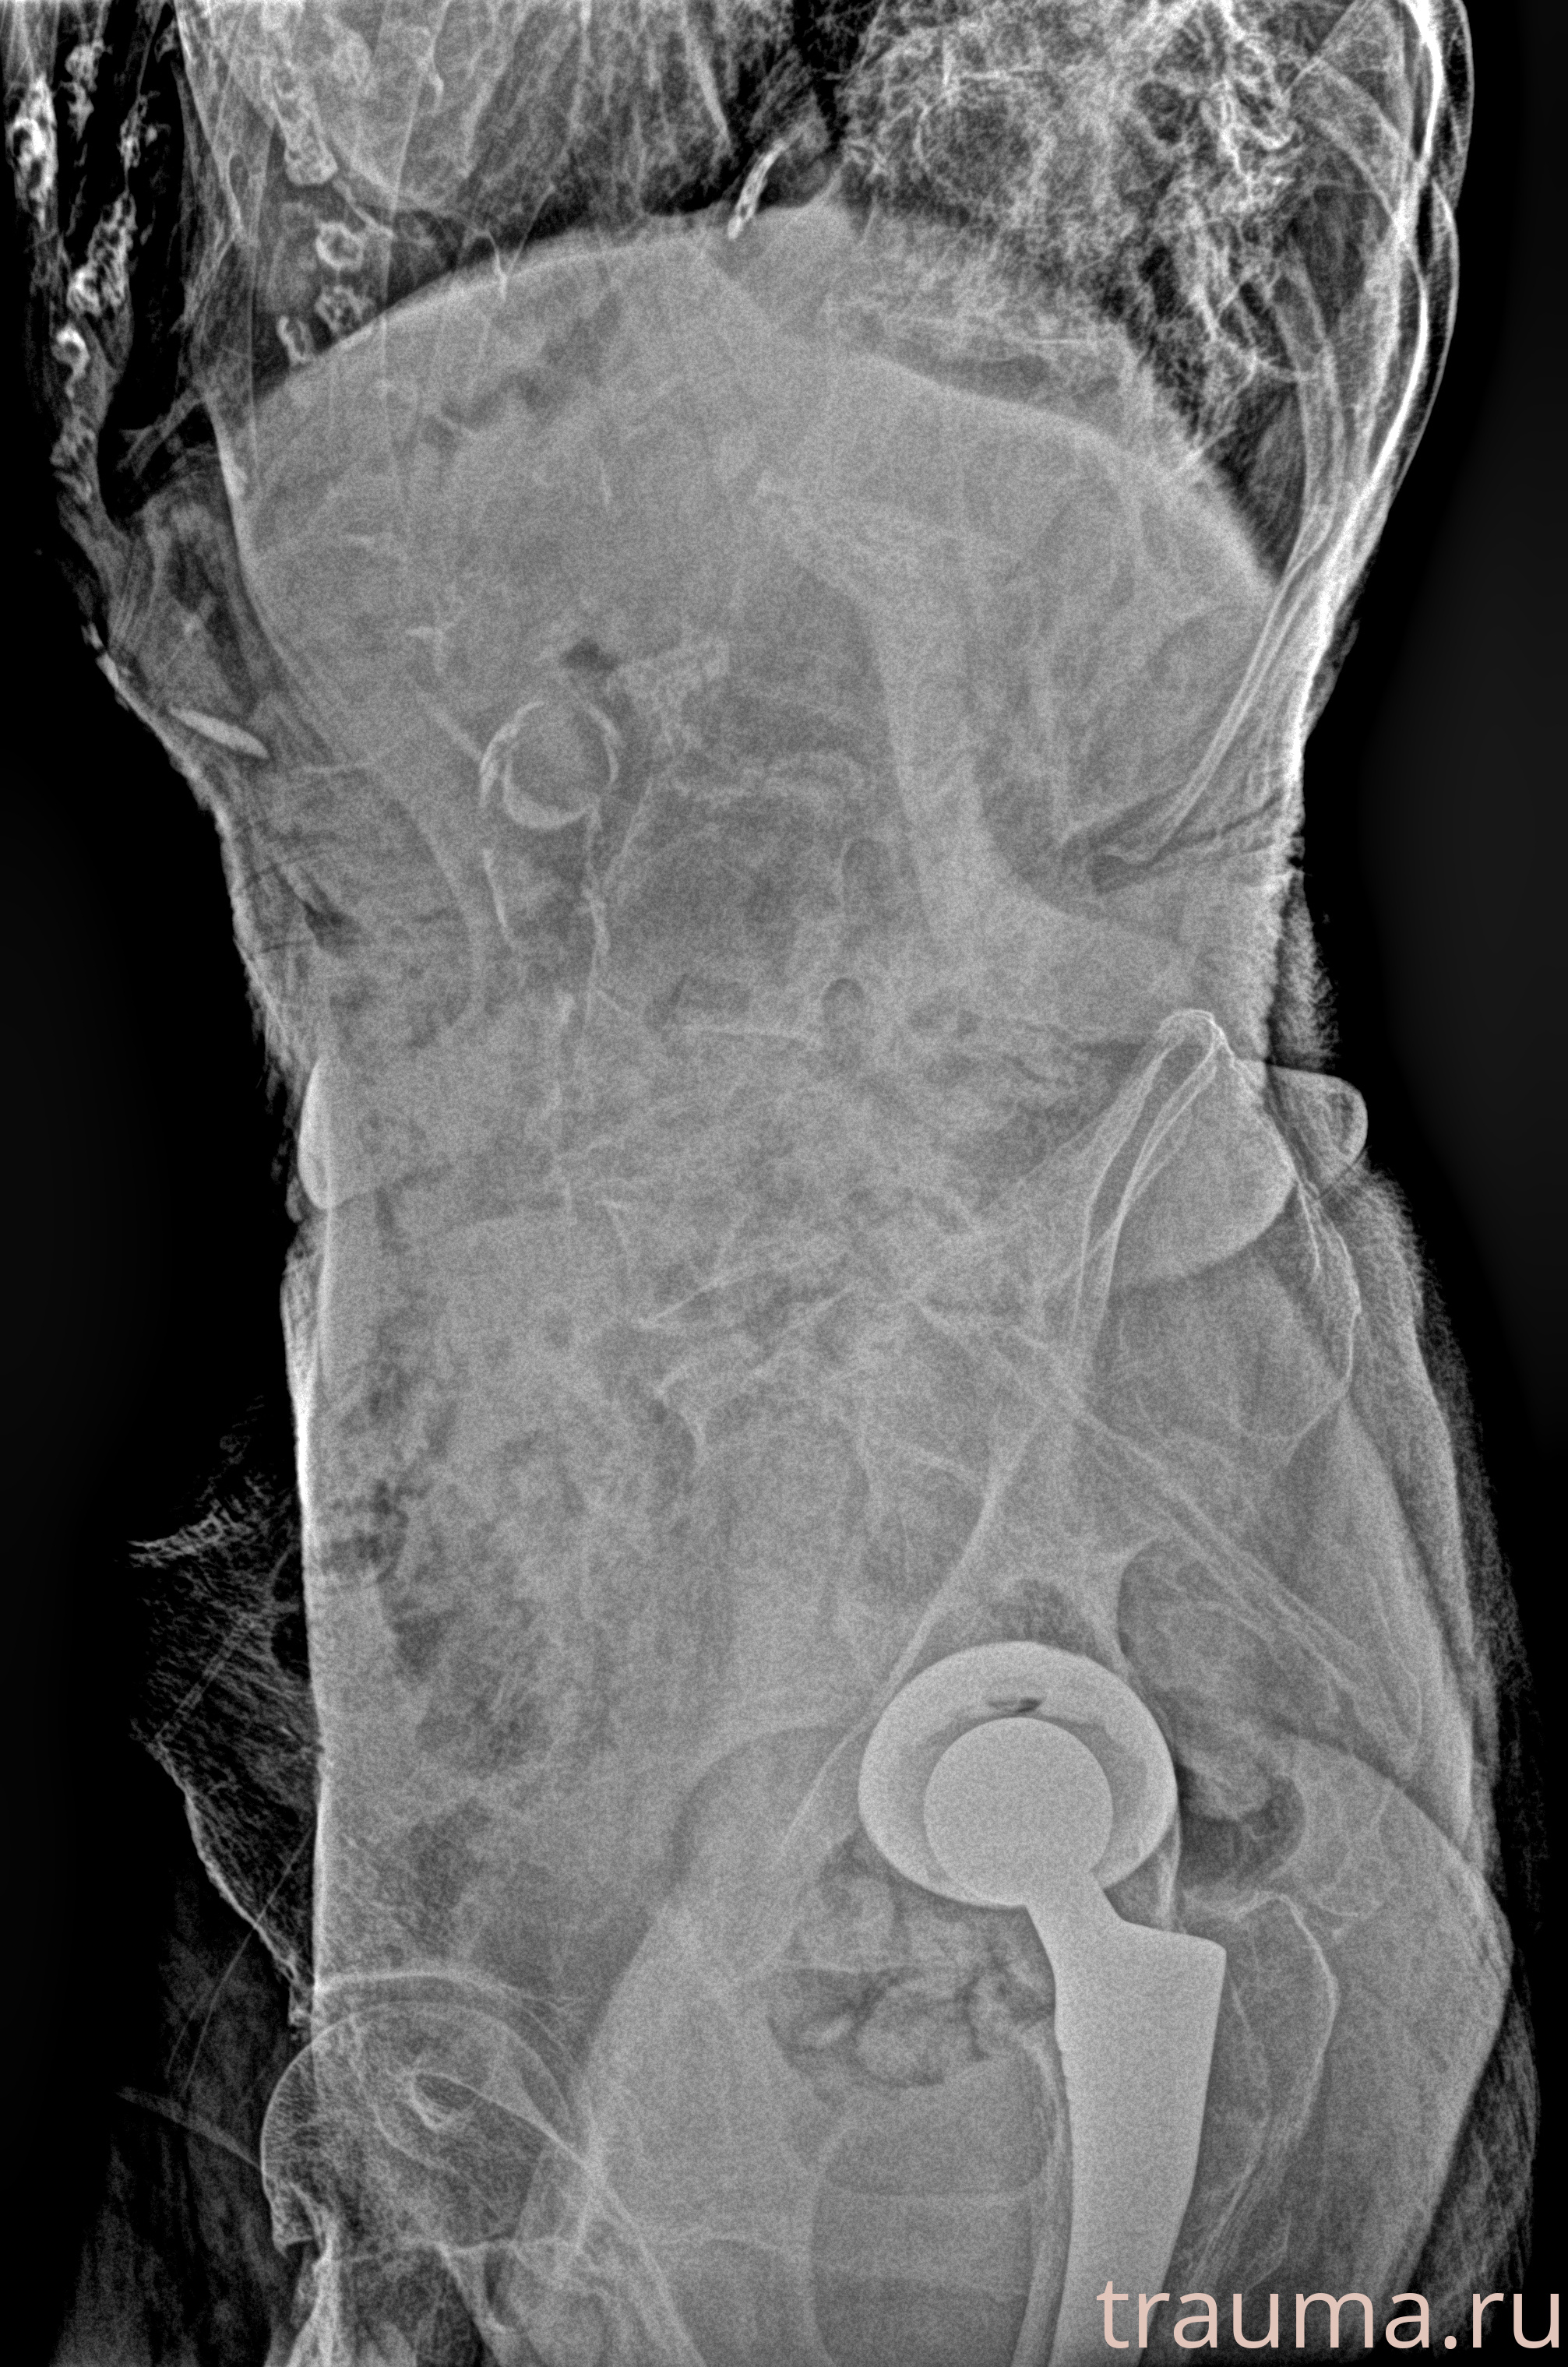

Рентген на дому: по вашему адресу приезжает врач-рентгенолог, травматолог-ортопед с мобильным рентгеновским аппаратом, проводит диагностику травмы или заболевания, делает необходимые рентгенограммы, дает рекомендации по дальнейшему лечению. Получить качественные снимки в домашних условиях возможно благодаря уникальной методике, разработанной МосРентген Центром для института  Склифосовского